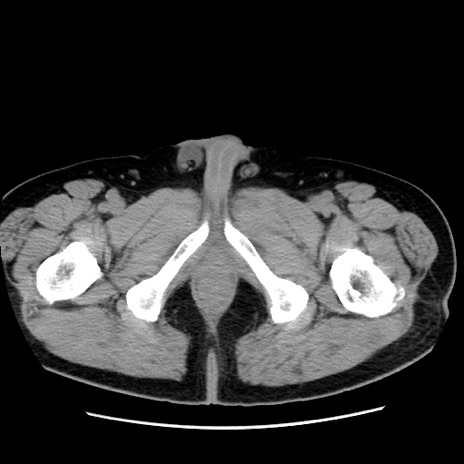

症例16(横断像)

【症例】 70歳代男性

【主訴】 腹痛、嘔吐

【現病歴】 約1ヶ月前より間欠的に腹痛と嘔吐あり、当院消化器内科を受診したところCTで多発する肝臓のLDAを指摘され、精査中であった。以降は消化器症状は安定していたが、2日前より嘔気と腹痛があり、同日より排便・排ガスが消失した。改善認めず、 本日、救急外来を受診した。

【既往歴】 大腸ポリープ切除後。

【身体所見】意識清明・会話良好、BT 36.3℃、BP 127/80mmHg、 P 80bpm、腹部:膨満あり、平坦・軟、上腹部正中および下腹部正中に圧痛あり、反跳痛なし、筋性防御なし。

【データ】WBC 7200、CRP 0.77